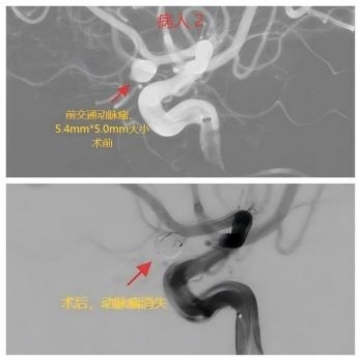

“急诊来了一位78岁蛛网膜下腔出血的女病人,CT考虑动脉瘤破裂,病情危重!”神经外科主任王磊的手机响起,传来值班医生的声音,“好,立即启动卒中绿色通道,通知介入导管室、麻醉医生迅速到位,准备急诊手术!”。当手术快结束时,急诊又入院一位72岁的同样的蛛网膜下腔出血的女病人,本该休息的医生们再次穿上沉重的铅衣与死神搏斗。经过一夜的战斗,两个病人手术均取得成功。

我院目前已建立了完善的脑卒中绿色通道,能够迅速、有效地完成从检查、诊断、急诊手术等流程。自今年1月份以来,我院神经外科已接诊了40多例动脉瘤破裂出血的患者。